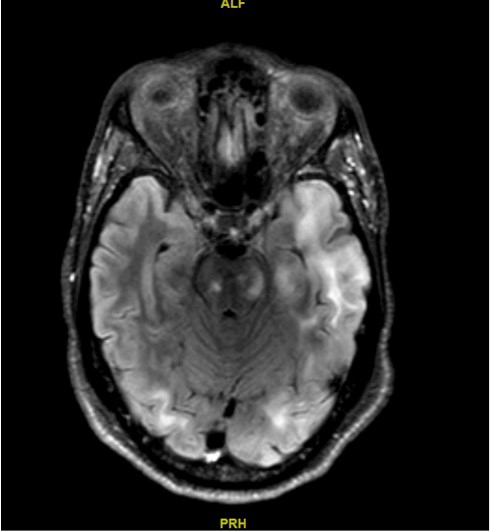

Une IRM est alors réalisée (coupe T2 FLAIR axiales) (images ci-dessous) : Les coupes T1 montrent des lésions hypo-intenses des mêmes territoires, mais aucune lésion ne prend le contraste.

Question 11 - Quel(s) est(sont) le(s) diagnostic(s) retenu(s) à ce stade ?

LEMP : hypo-T1 hyperT2, pas de prise de contraste.

Vous retenez le diagnostic de leucoencéphalopathie multifocale progressive.